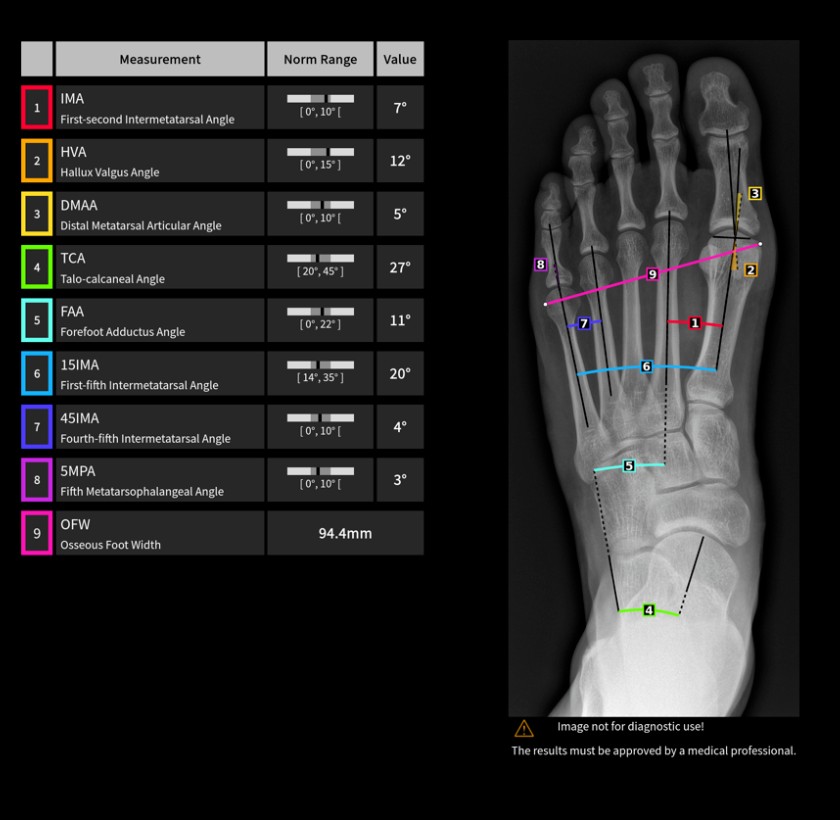

IB Lab FROG ist eine vollautomatische, radiologische Bildverarbeitungssoftware, die den Benutzer bei der Vermessung der Fußgeometrie auf Röntgenaufnahmen des Fußes unterstützen soll.

Die Ergebnisse werden in einem grafischen Befund zusammengefasst, dem Original-Röntgenbild beigefügt und automatisch im PACS-System gespeichert. Die KI erleichtert die Überwachung des Krankheitsverlaufs.

Radiologische Befunde, Messungen und Ergebnisse, einschließlich: